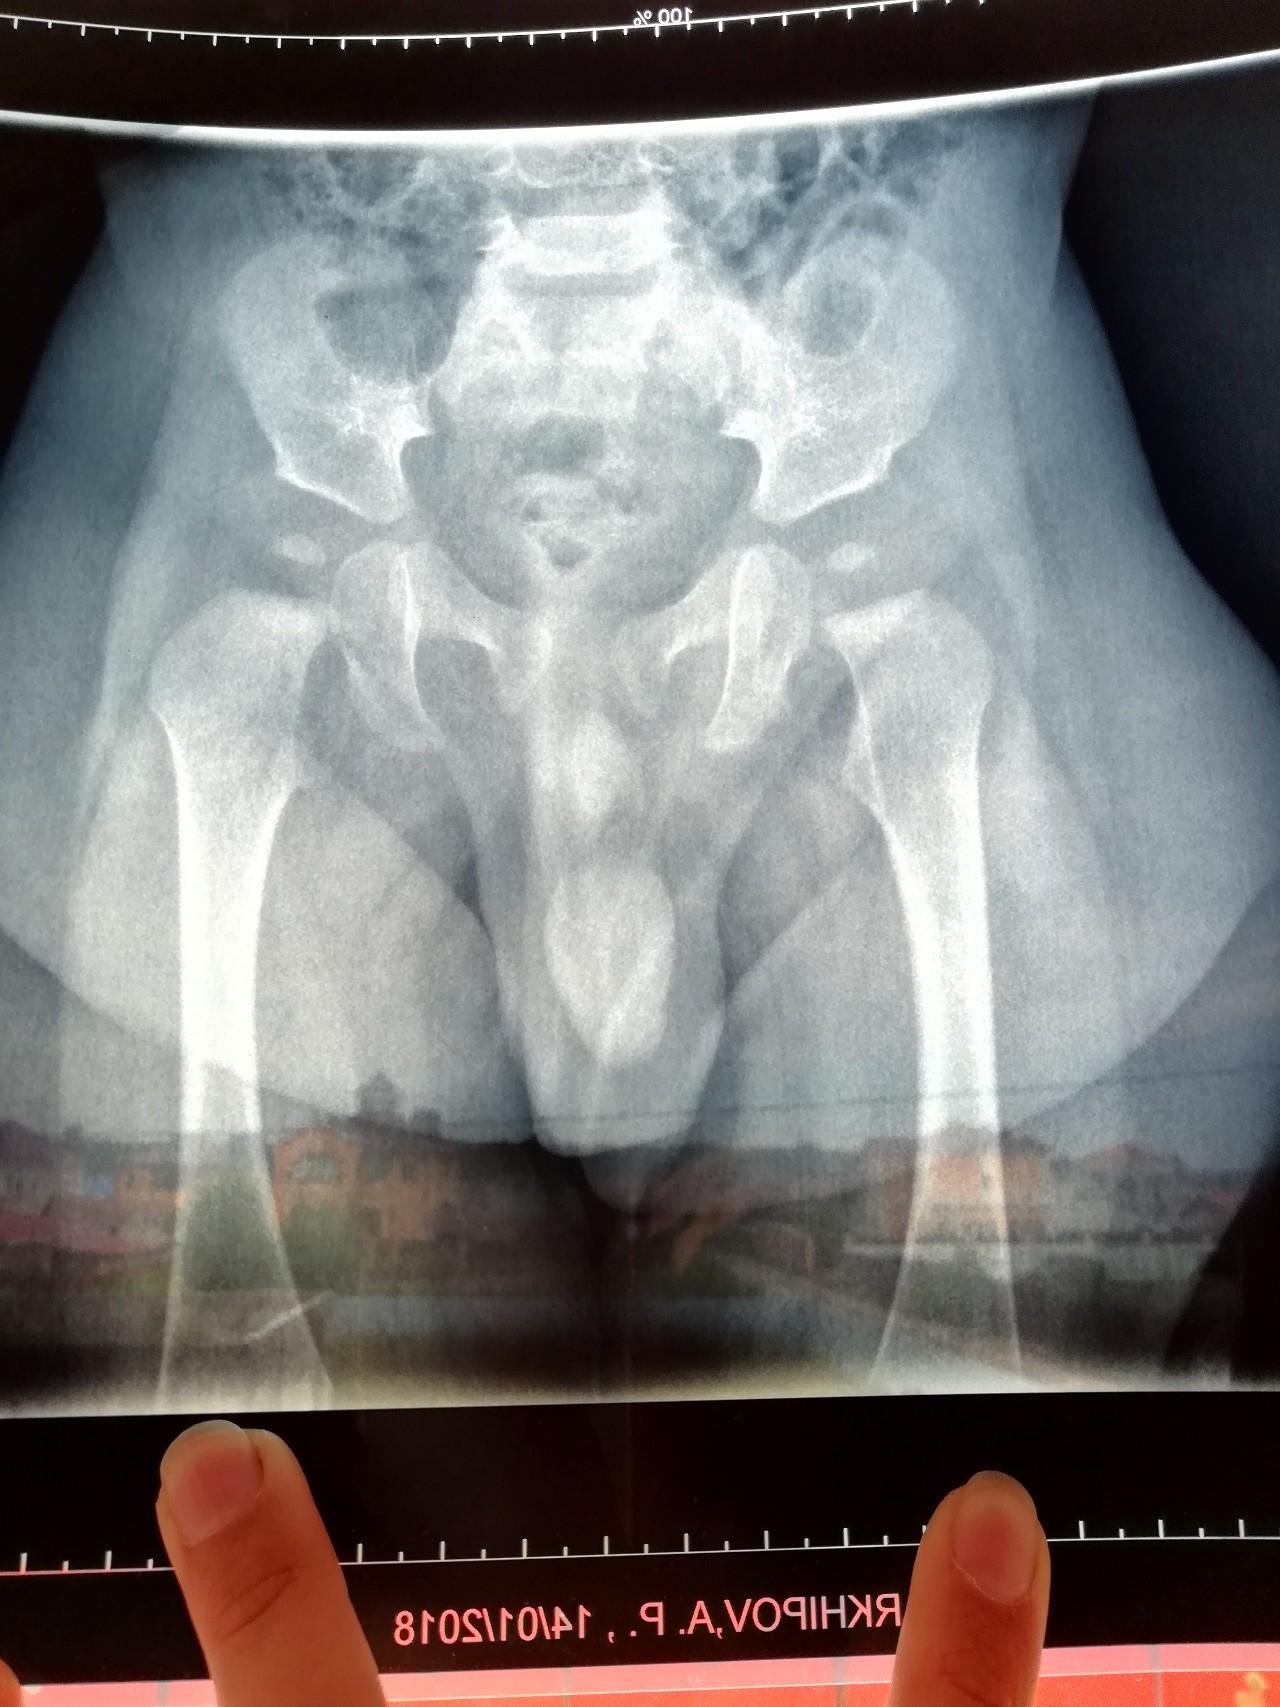

Рентгеновский эффект создает фантастические композиции в этих фотографиях девушки, чье тело становится прозрачным, демонстрируя скелет и внутренние органы. Она позирует в разных позах, ее силуэт светится загадочным свечением. Каждый кадр передает атмосферу научной фантастики и медицинского искусства. Ее кожа кажется полупрозрачной, позволяя увидеть кости и мышцы. Фотографии рассказывают о хрупкости человеческого тела и его внутренней красоте. Девушка то стоит в задумчивости, то делает грациозное движение. Эти иллюстрации вдохновляют на размышления о человеческой анатомии и уязвимости. Каждая картинка - это момент прозрения, когда внешнее уступает место внутреннему. Девушка воплощает образ современной Медузы, сочетающей красоту и загадочность.